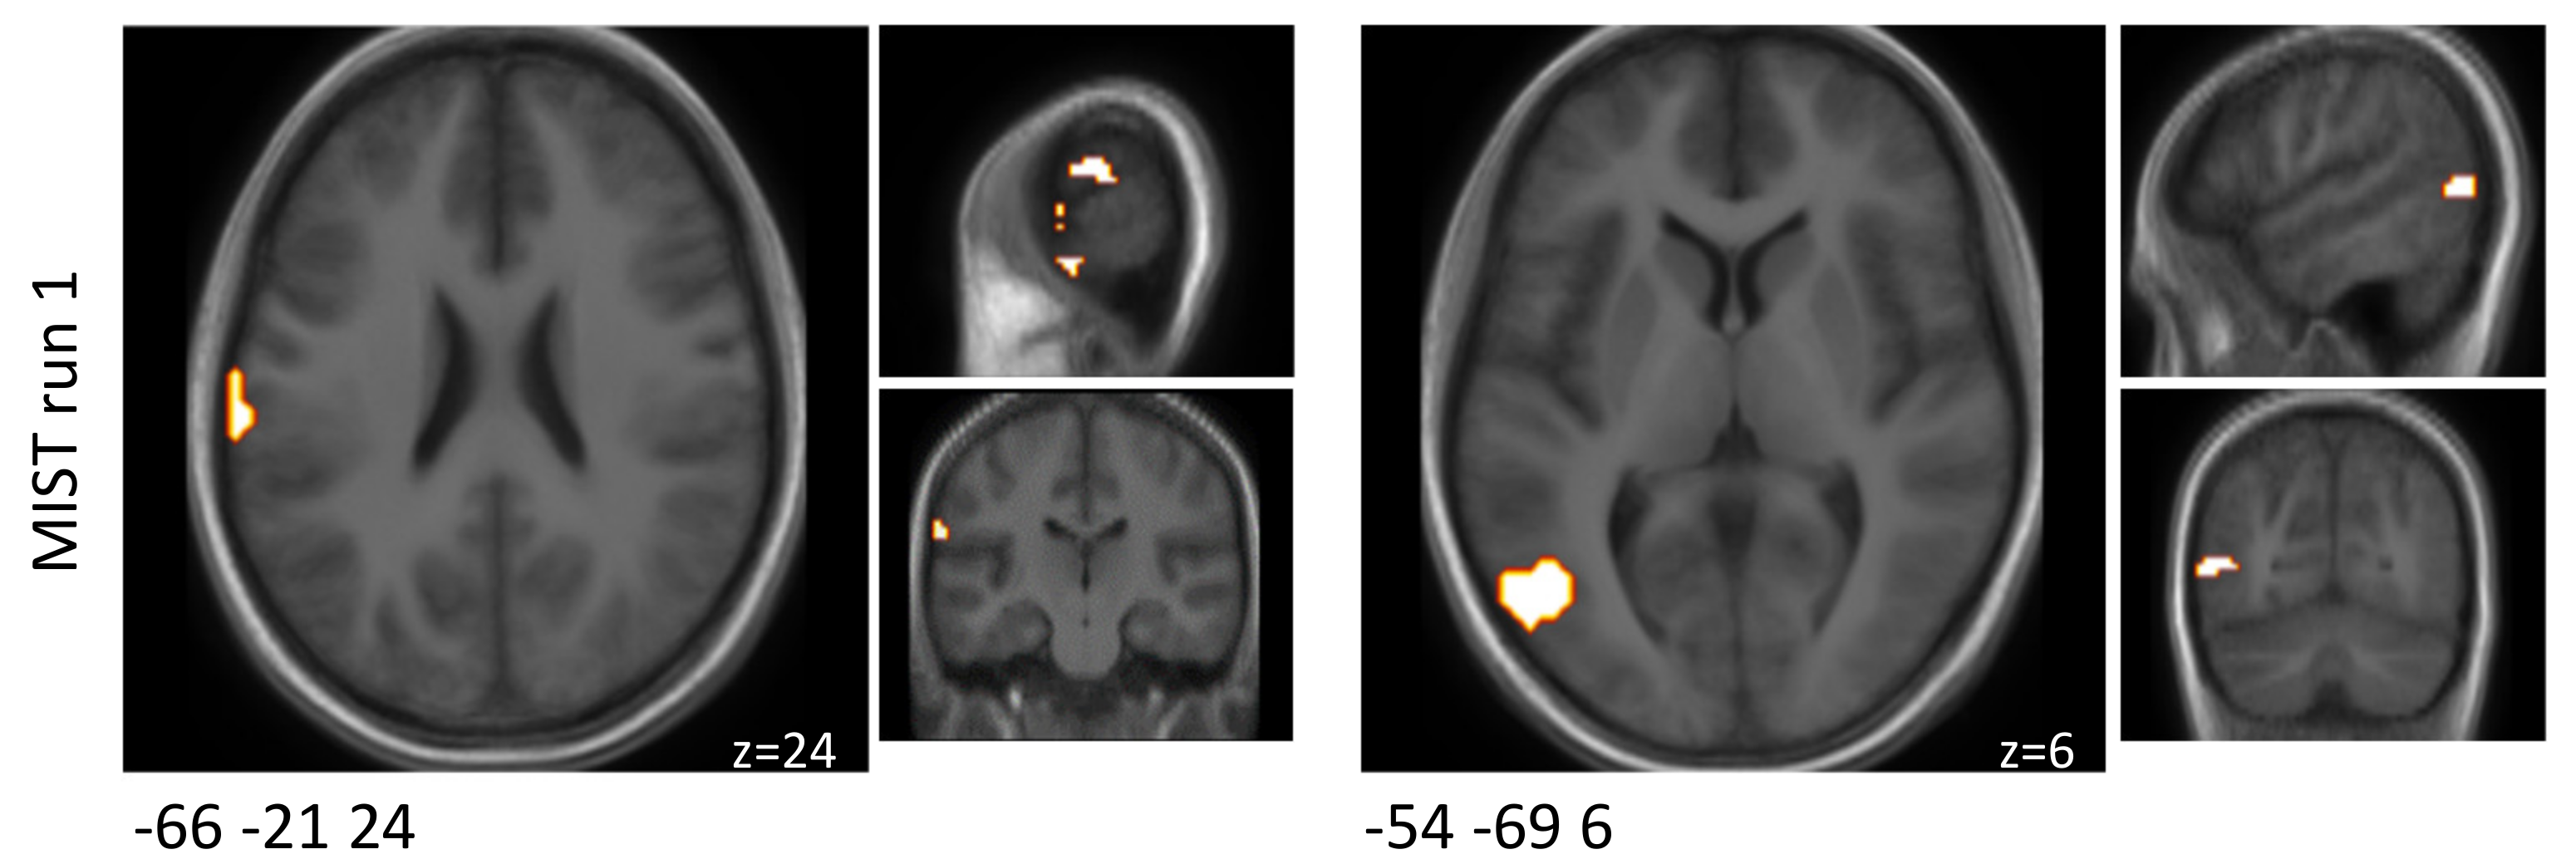

Using cluster-based analysis, activation (probiotics > placebo) (p < 0.1, without correction for multiplicity) was observed in two clusters when comparing the interventions with respect to the differential activity evoked by the challenge paradigm in MIST run one. Those two clusters were located in the rostroventral and dorsolateral areas. In MIST run two and three, no significant differences were found by cluster-based analysis. The results separated by the three MIST runs are reported in Table 2 and Figure 2.

Clusters that were found to be associated with changes in brain activity (p < 0.1) between both interventions when comparing the experimental and control condition before multiplicity correction during the MIST paradigm.

Figure 2.

Schematic visualisation of clusters that were found to be associated with changes in brain activity (p < 0.1) when comparing the probiotic and the placebo interventions (probiotic > placebo) and when comparing the experimental and control condition before multiplicity correction during the MIST paradigm. Clusters are superimposed on average anatomical scans. Clusters can be identified by the coordinates of their peak (x y z).